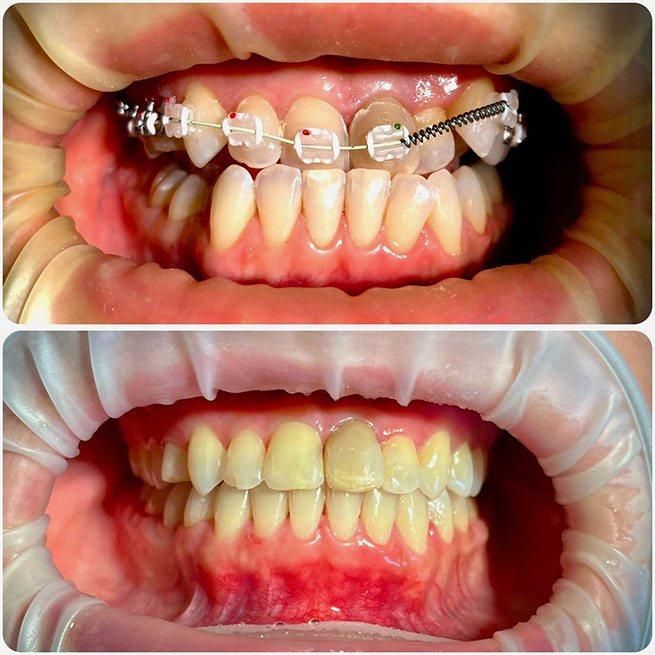

Брекет-системи – класичне та ефективне рішення для виправлення прикусу та вирівнювання зубів. Я працюю з:

- Керамічними брекетами (естетичний варіант);

- Сапфіровими брекетами (майже непомітні);

- Комбінованими брекетами (поєднання різних матеріалів для оптимального результату).